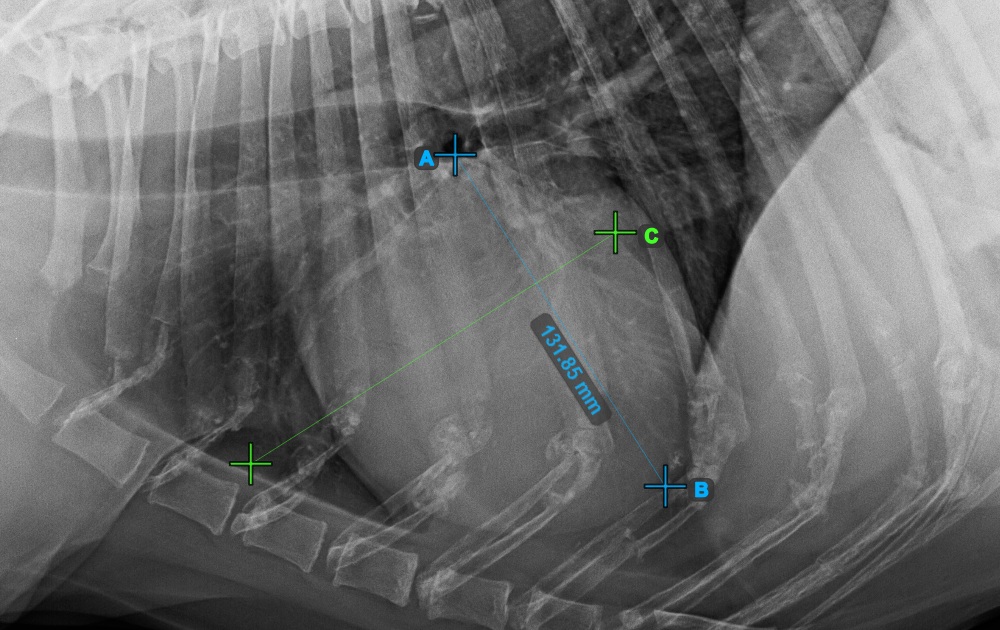

Start the measurement by marking the Bifurcatio tracheae, near the top of the heart.

The image below represents a typical placement of the Bifurcatio tracheae point.

Complete the long axis of the heart by marking the Apex point, near the bottom of the heart.

The image below represents a typical placement of the Apex point.

Continue the measurement by marking the widest right (cranial) point of the short axis of the heart.

The image below represents a typical placement of the most cranial point on the short axis of the heart.